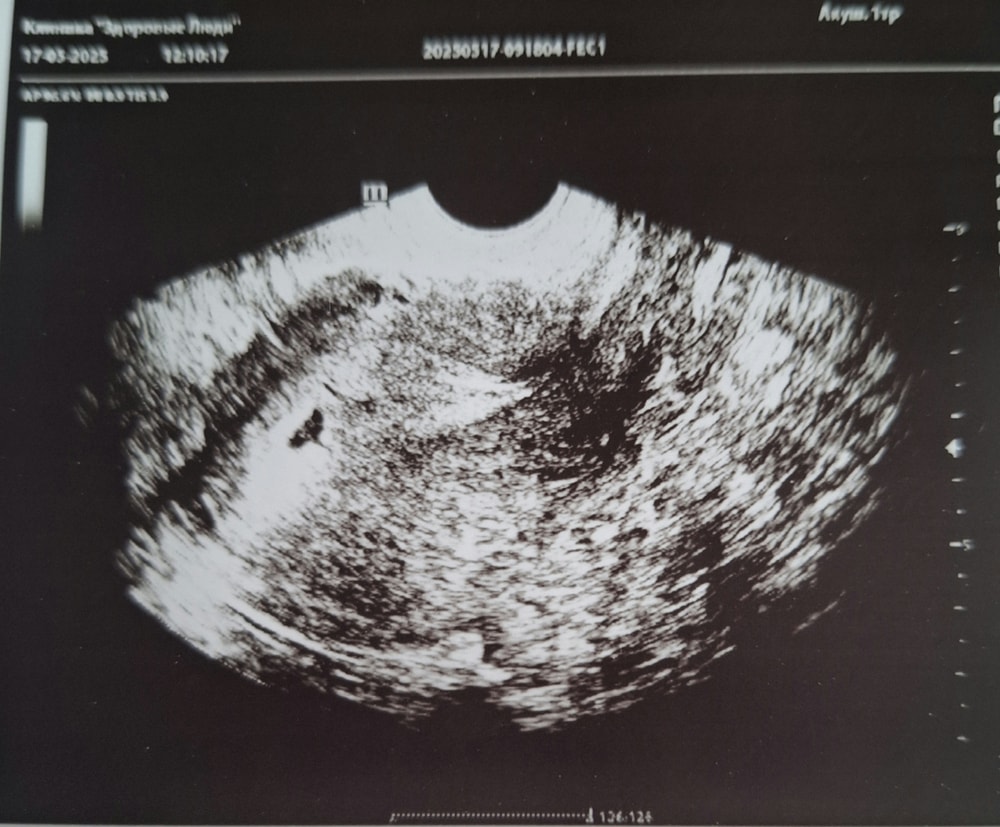

Сходила я сегодня на первое узи , посмотреть местонахождения пя . Хорошо прикрепился в нужное место , свд 7 мм , срок 5 недель и 3 дня . Через 2 недели повторное узи , уже будет эмбриончик и сб+ 🫶🏻🙏🏻🤞🏼